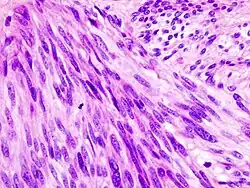

Feingeweblich zeigen GISTs entweder ein rein spindelzelliges (69 %), epitheloides (12 %) oder gemischt spindelzelliges/epitheloides (20 %) Bild.[27] Immunhistochemisch exprimieren die überwiegende Mehrheit der GISTs die Marker c-Kit (CD117; 87 %) und PDGFA (66 %).[28] In 30–80 % der Fälle lassen sich auch glattmuskuläre Marker nachweisen; der zuverlässigste von diesen, Desmin, wird jedoch nur von einer Minderzahl der GISTs exprimiert. Eine CD 34-Positivität kann in bis zu 70 % der Fälle demonstriert werden.[29]